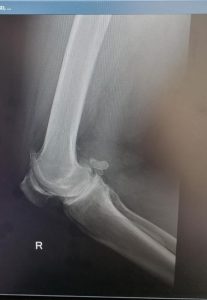

KNEE REPLACEMENT

As the knee ages it may come to a point where cartilage has eroded away to expose bone. Bone grinding on bone as a person is walking is very painful. Fortunately orthopaedic science has evolved to a solution whereby the knee can be replaced with a mechanical prosthesis.

Presently, the results are generally very good with excellent pain relief and mobility after the operation. Longevity of the prosthesis has improved to a point where the 10 year survival is more than 95% in some series.

As all surgery, the procedure is not entirely risk free. Deep venous thrombosis at 1% incidence and infection at 0.4% are most common complications, but stiffness, bleeding, nerve injury etc. can occur.

Below see the pre operative pictures of a normal knee, a diseased knee and a replaced knee.